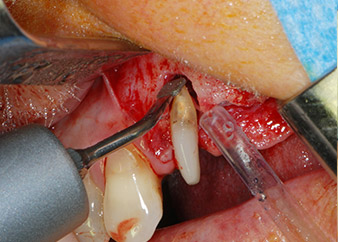

Einen Monat nach dem Eingriff waren sowohl die Schmerzen als auch die Entzündung an Zahn 24 minimal, die Zahnbeweglichkeit lag jedoch noch bei Miller-Klasse 2. Nach Freilegung und Reinigen des infizierten periapikalen und periradikulären Gewebes wurde das Ausmaß des Knochendefizits deutlich (Abb. 2 und 3).

An der bukkalen Wurzel fehlte der gesamte vestibuläre und distale Knochen. Das Attachment beschränkte sich weitgehend auf die palatinale Wurzel, was die anfängliche schlechte Prognose unterstreicht. Auch Zahn 27 wies ein verringertes horizontales Attachment (vgl. Abb. 12) und eine kleine apikale Aufhellung (Abb. 1) auf, allerdings ohne klinische Symptome.

Zunächst wurde in einem Versuch, das Paro-Endo-Problem zu lösen, an der verbleibenden Wurzeloberfläche ein vorsichtiges Debridement mit einem piezochirurgischen Gerät vorgenommen (Piezomed, W&H) (Abb. 4); dann wurde der Apex mit dem gleichen Instrument im Sinne einer WSR abgetragen, um das verbleibende infizierte apikale Gewebe zu entfernen (Abb. 5). Eine retrograde Füllung war nicht notwendig, da die orthograde Füllung gerade revidiert worden war.